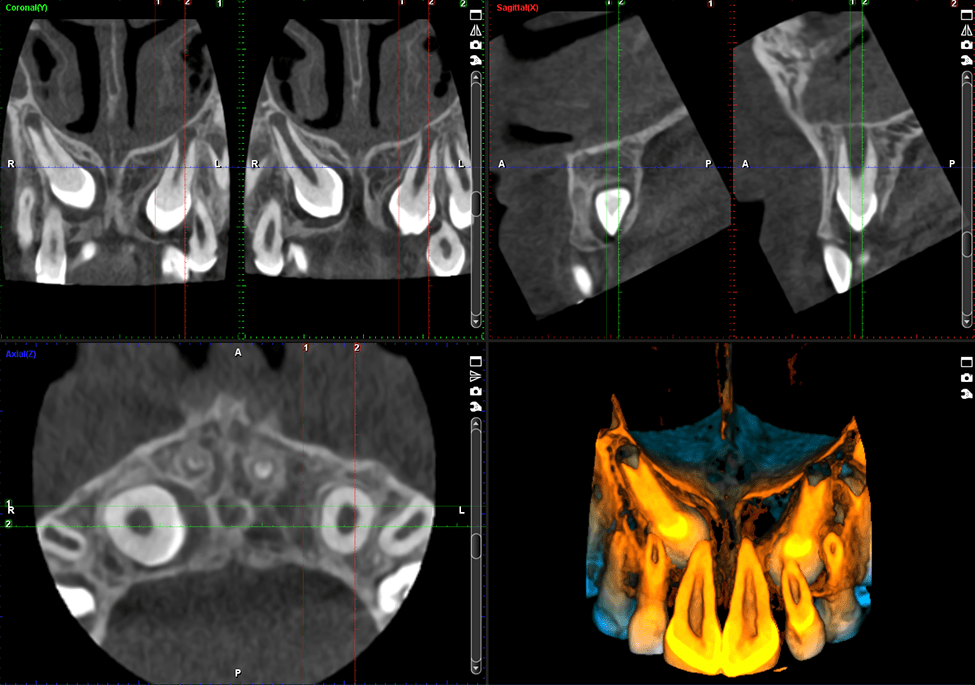

Zobacz najdrobniejsze szczegóły

Tryb endodontyczny oferuje niezwykle wysoką rozdzielczość przy rozmiarze voxela 75 µm. Tryb ten jest idealny do wyodrębniania najdrobniejszych szczegółów, umożliwiając dokładną diagnozę i planowanie leczenia.

Idealny do wizualizacji aparatów ortodontycznych

Protokół obrazowania stomatologicznego Planmeca Promax 3D Classic jest idealny do prac ortodontycznych: metalowe części aparatów pokazują się na zdjęciach z naprawdę imponującą dokładnością. Urządzenie jest również certyfikowane do stosowania z protokołem leczenia SureSmile.